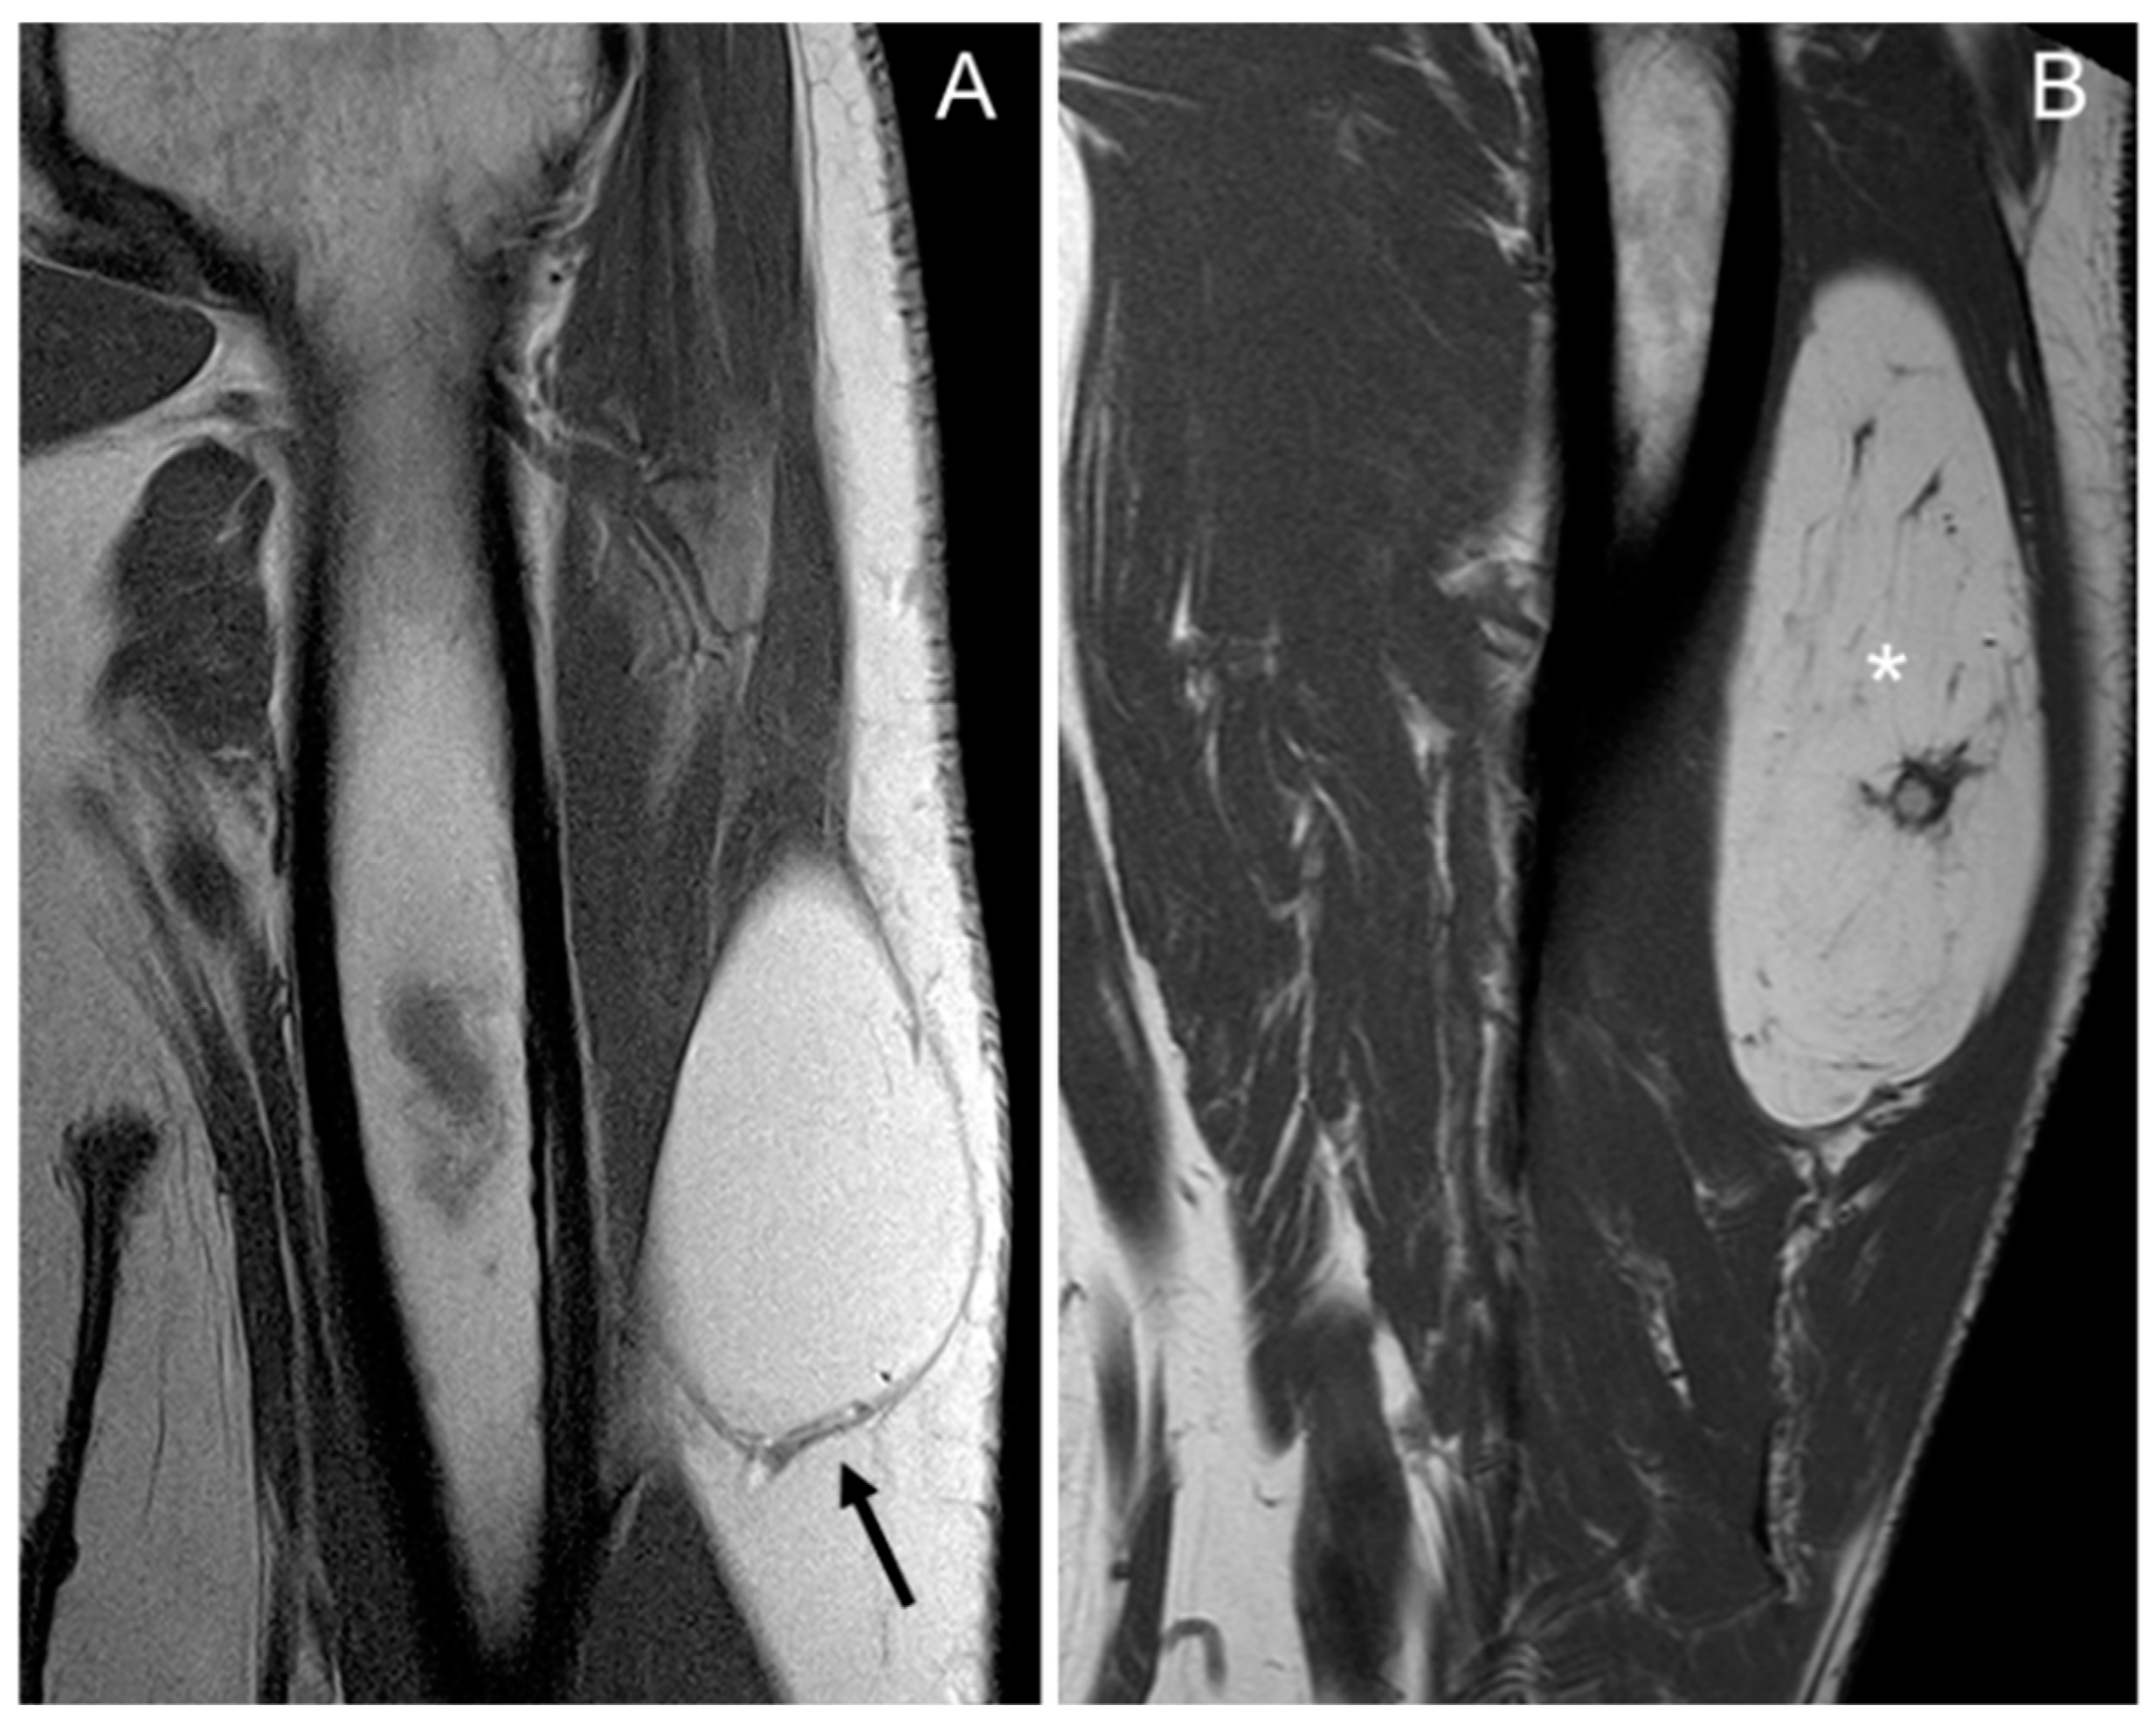

In total, 97–100% of tumors with homogeneous fat signal in the three sequences (p value < 0.001) were lipomas, and 55–61% of lesions with heterogeneous signal were lipomas (Figure 1).

In our series, the lipomas showed both homogeneous and heterogenous fat signal intensity, while all ALTs were heterogenous tumors. Based on this criterion—the signal intensity of the tumor on MRI—some lipomas may be misinterpreted as ALT, but the opposite is not true; no ALTs would be misdiagnosed as a lipoma. With homogeneous hyperintensity on SE T1 and TSE T2 sequences, and complete suppression of the fat signal using fat suppression techniques, the diagnosis of lipoma can be made with high confidence. In contrast, heterogeneous tumors may be either a lipoma or an ALT (Figure 4) Therefore, homogeneous signal rules out ALT, while heterogeneous signal does not rule out lipoma (Figure 1).

Figure 1. Coronal T1 weighted (T1W) images: (A) homogeneous lipomatous (completely fatty) tumor in the left arm (arrow), and (B) heterogeneous lipomatous mass in the left thigh, with one non-fat nodule (*) and multiple septa. The diagnosis for both tumors is lipoma, confirmed as MDM2 negative.